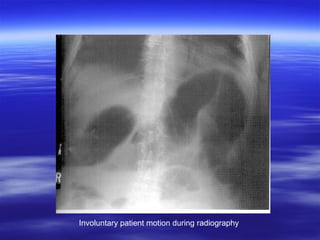

Motion blur (unsharpness)

Involuntary patient motion during radiography

Motion Unsharpness

 Voluntary

referred to as motion that

under conscious control of the will.

 Involuntary

motion attributed to the

physiological action of the of the body